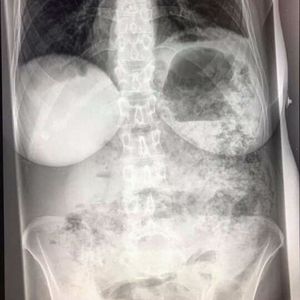

50yrs .abdomen pain plz explain cause

Look for D.D. of abdominal pain. If there is multiple air-fluid levels it means intestinal obstruction